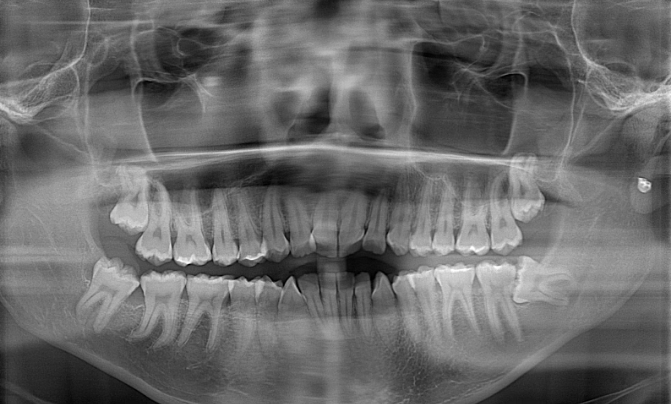

Yesterday I had 4 wisdom teeth extracted (2 upper 2 lower) because the Ortho (male) said I needed to before I can get braces.

In the photo you still see the wisdom teeth because it's an old X-ray

I got my 4 wisdoms pulled out and showed up ready to get braces but a different Ortho (female) than the last one says I either need to remove one premolar on the bottom or 4 premolars (2 upper and 2 lower) before I can completely get braces

I said let me get just 1 premolar removed but then she said she's gonna get 4 removed because it will produce a better result

The reason she is saying to remove the premolars is to fix my teeth protrusion and to create room to fix my crowding teeth